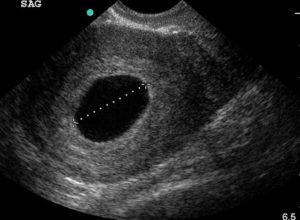

Пустое плодное яйцо или отсутствие эмбриона фото:

Определяется данная патология, на первом УЗИ, на 5-6 неделе беременности. Если нет эмбриона в плодном яйце на мониторе аппарата УЗ-исследования, то врачом выносится диагноз анэмбриония. В некоторых случаях рекомендуется пройти повторное исследование на 7-8 неделе или отследить динамику ХГЧ. Дважды подтвержденный плод без эмбриона является поводом к прерыванию беременности.

При условии отсутствия патологий размеры нормального плодного яйца постепенно увеличиваются. Так в среднем на 4 неделе можно визуализировать ПЯ до 5 мм, после 5 недели размер составляет 6-7 мм.

Существенно увеличение происходит на 6-7 неделе, размеры ПЯ достигают от 11 мм до 16-17 мм, а уже на сроке после 8 недель нормально плодное яйцо четко визуализируется и диаметр его равен 18-22 мм.